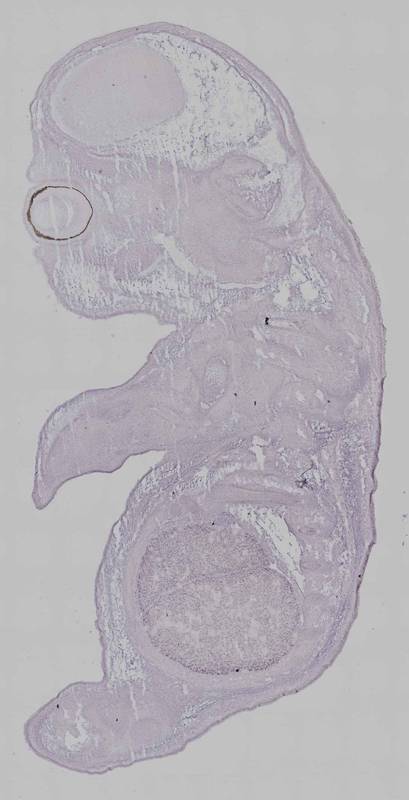

Specimen Additional file 4 Hpn: embryonic day 14.5 (more )

TS22: pancreas epithelium Present Embryo_G0709_1_1A